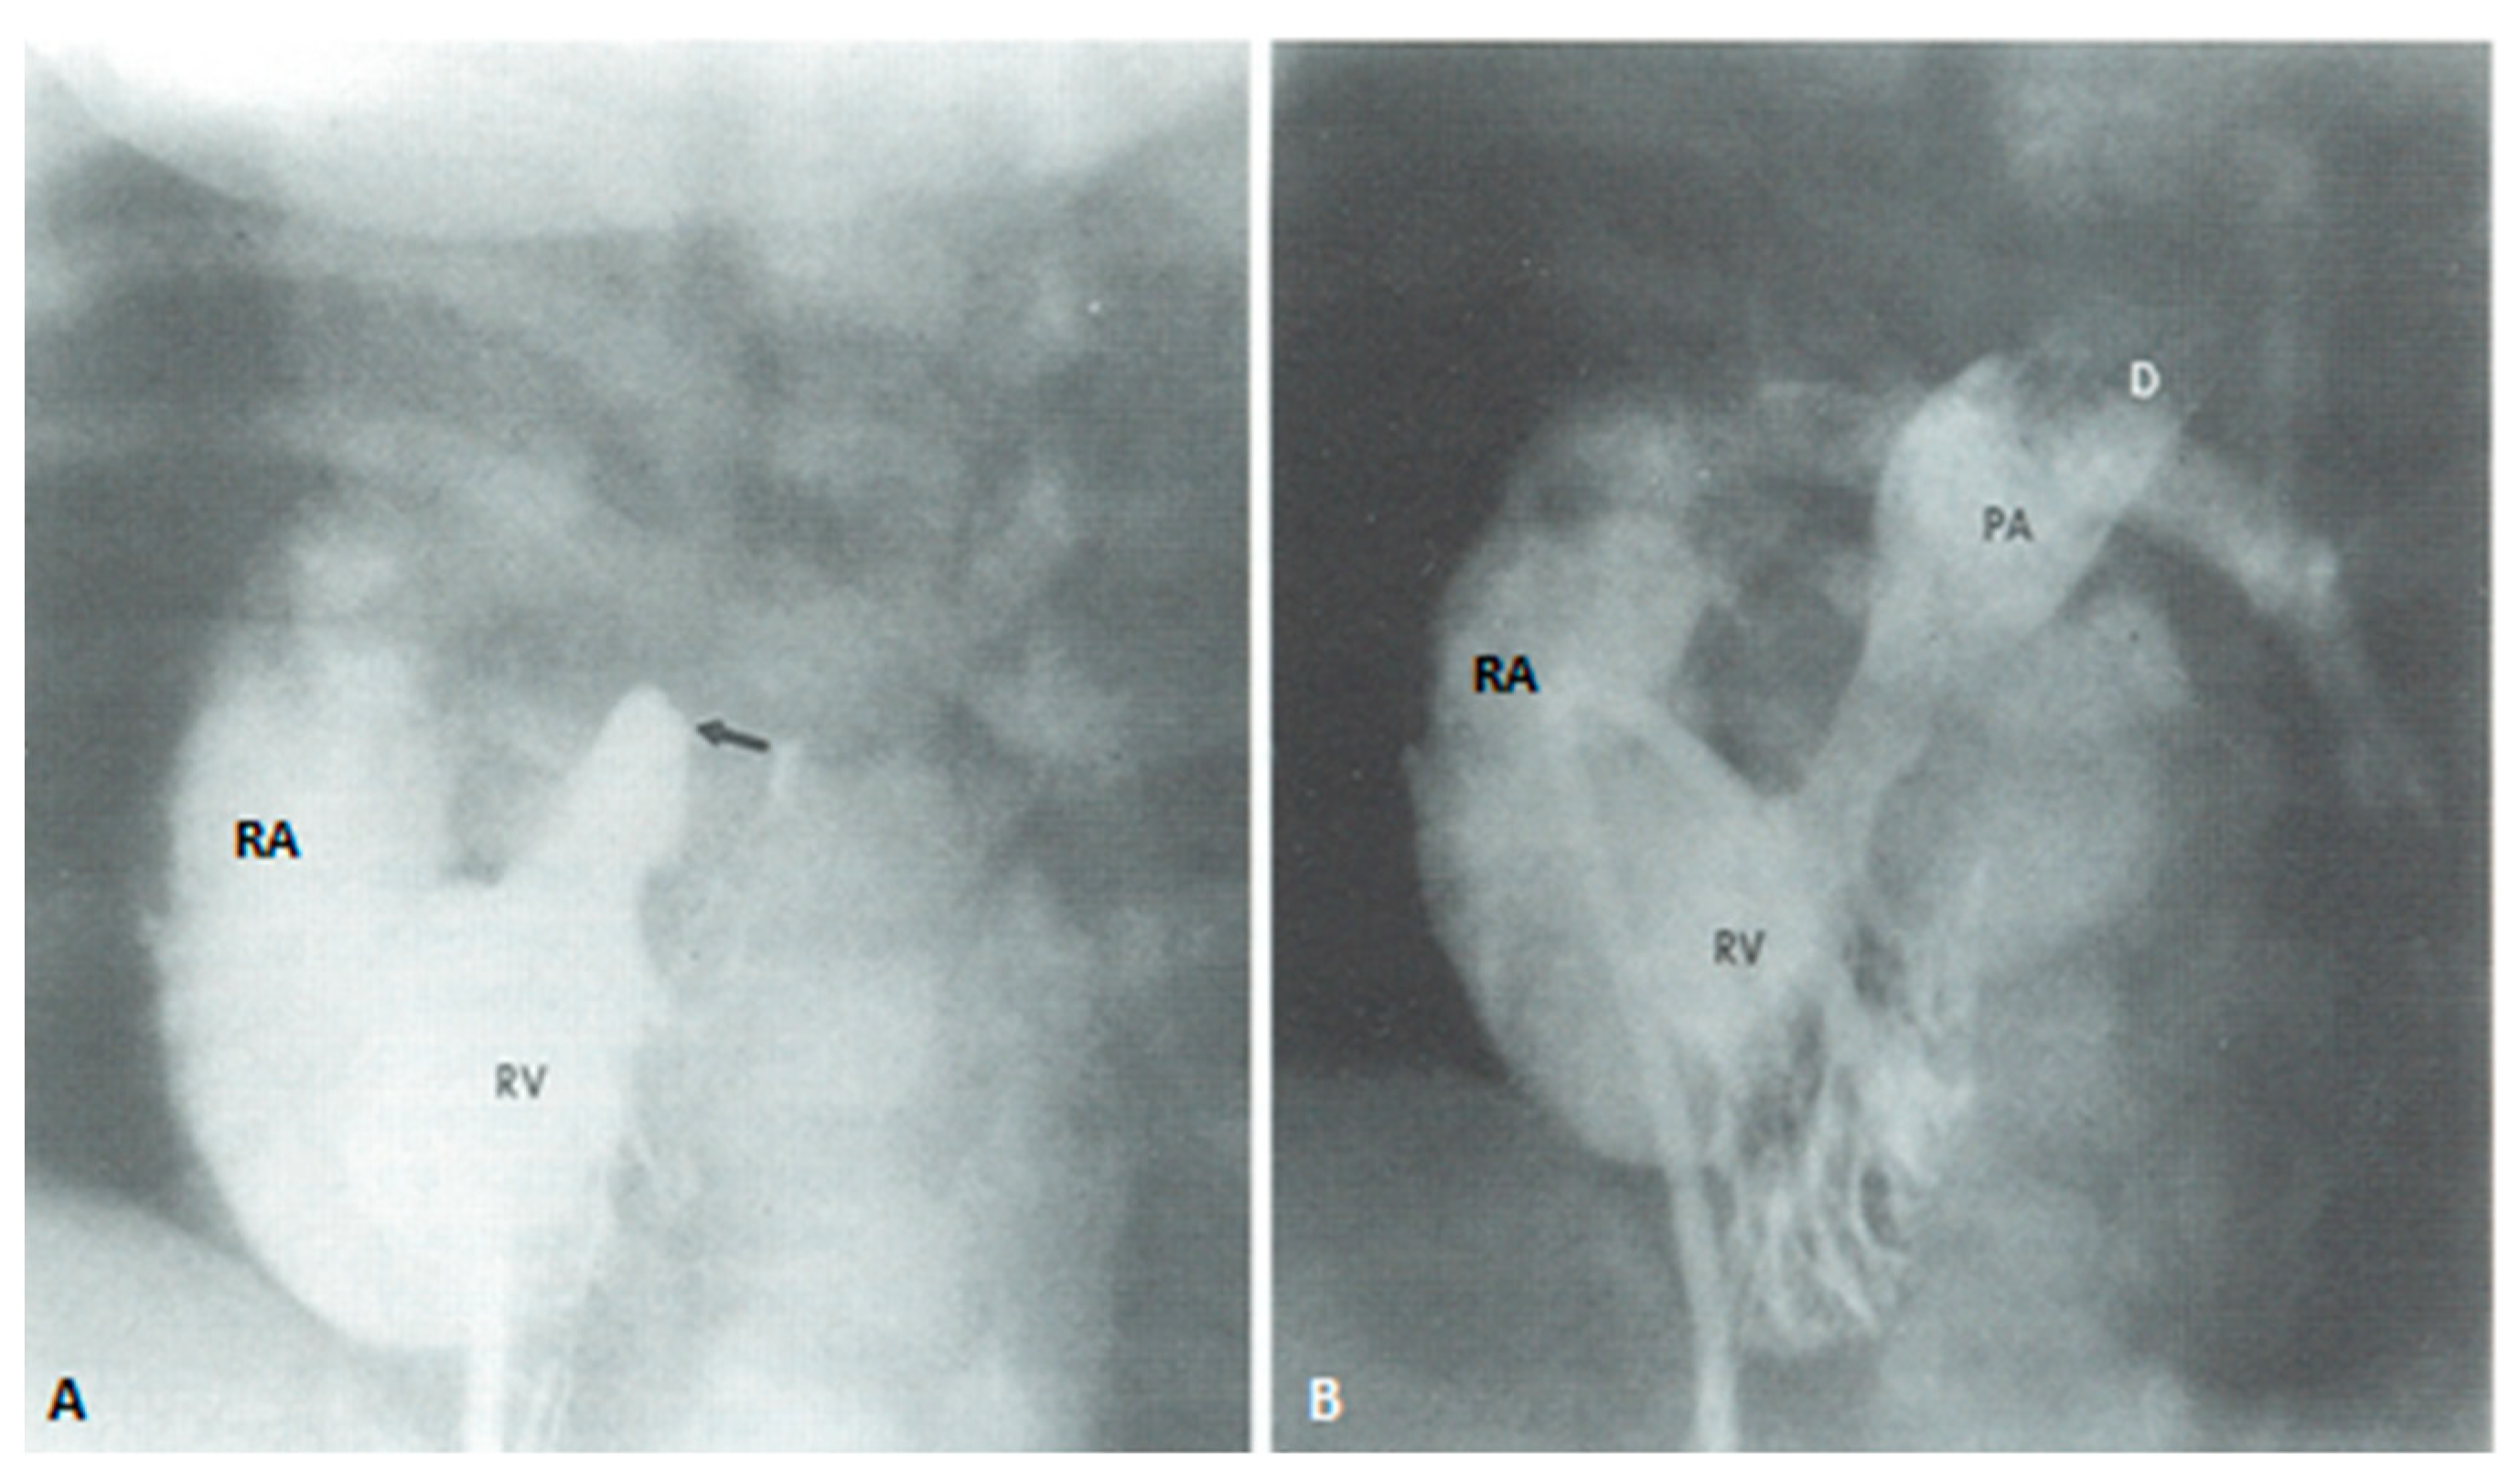

At the time of presentation, usually in the early infancy, palliation depending the physiological abnormality (modified BT shunt or pulmonary artery banding) (Figure 7) is performed after initial stabilization.

The pathophysiology produced by multiple defects in the above two entities is similar to that described for tricuspid atresia and consequently the management is similar [7,120,121]. The general objective is to accomplish Fontan circulation by staged total cavopulmonary connection. In young babies with decreased pulmonary blood flow, a modified Blalock–Taussig shunt (Figure 7A) is performed and if the pulmonary blood flow is increased, PA banding (Figure 7B) is undertaken. Relief of aortic coarctation, if present, should be provided. Subsequently, bidirectional Glenn (Figure 8 and Figure 9) and Fontan completion (Figure 10 and Figure 11) are undertaken as described in the “Tricuspid Atresia” section. Similarly, subaortic obstruction should be addressed by bypassing the obstruction by Damus–Kaye–Stansel, again as described in the “Tricuspid Atresia” section.